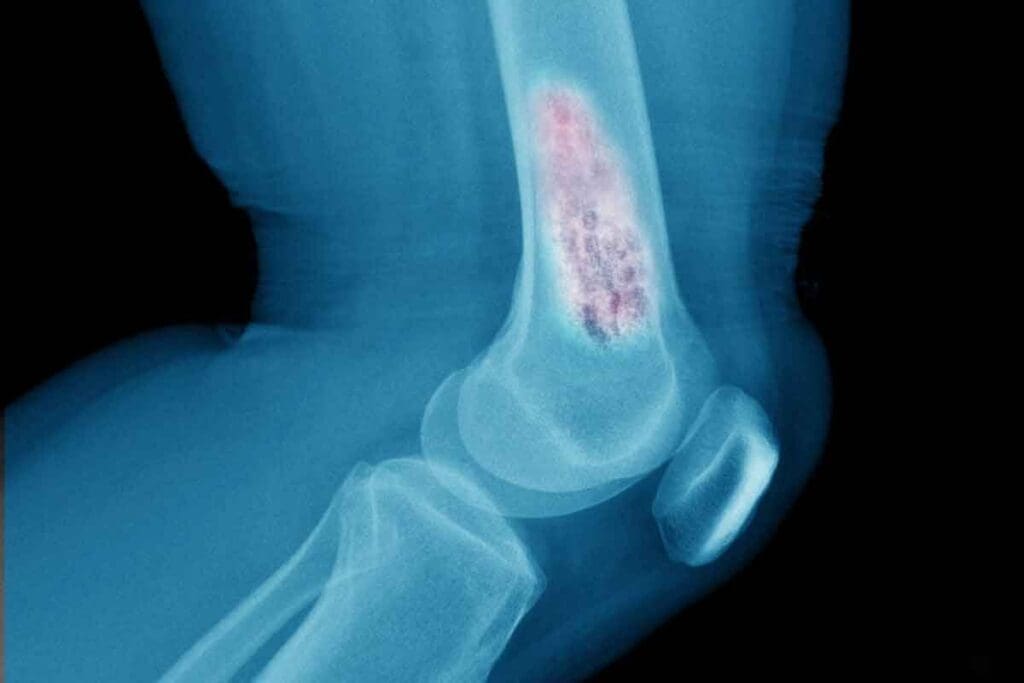

Ewing sarcoma is a fast-growing cancer that mainly affects kids and teens. It’s rare and aggressive, making it hard to diagnose and treat. It can grow in bones or soft tissues.

Ewing sarcoma grows quickly and can spread to places like the lungs or bones. It’s a very aggressive tumor that needs quick and strong treatment. The exact cause is not known, but it’s thought to be due to genetic changes.

The symptoms of Ewing sarcoma depend on where and how big the tumor is. Common signs are pain, swelling, and trouble moving. Getting a diagnosis early is very important for better treatment results.

To diagnose, doctors use X-rays, CT scans, and MRI scans. Then, a biopsy confirms if it’s cancer. Getting the diagnosis right is key to knowing how far the disease has spread and planning treatment.